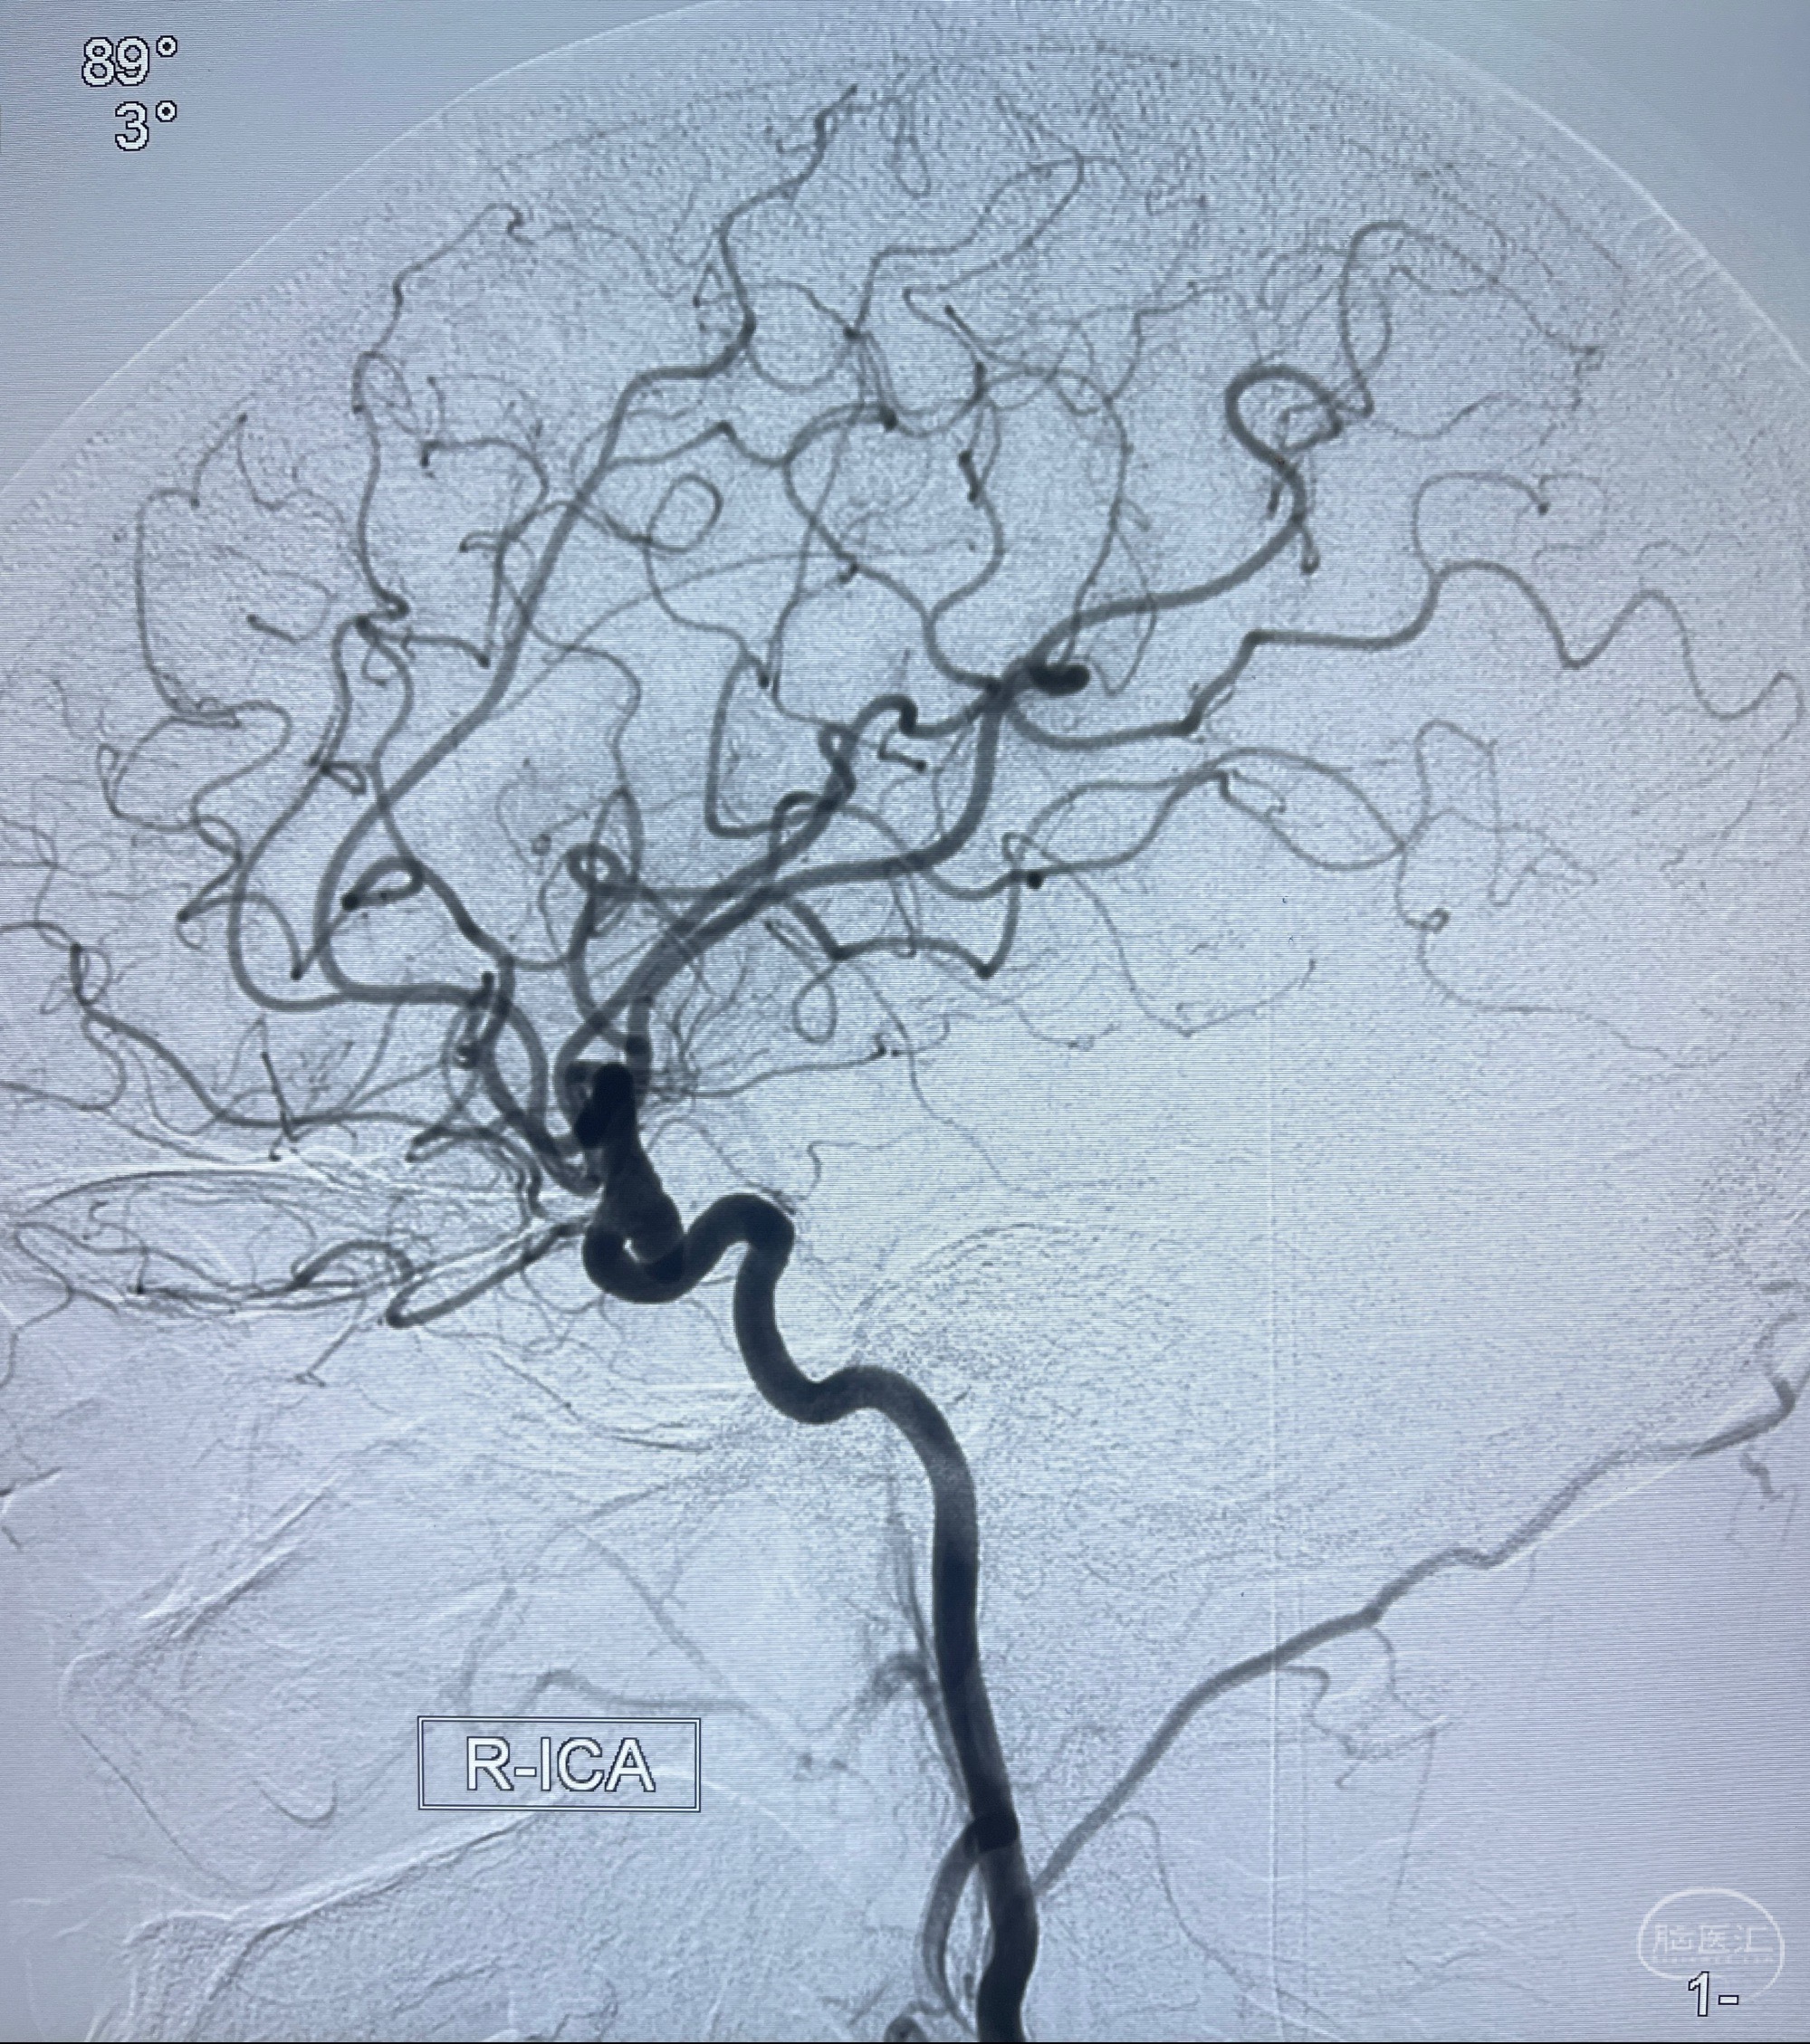

2023.07.25 泰州市人民医院查头颅CTA提示右侧C6段瘤样突起,建议DSA检查;

CTA示:右侧颈内动脉C6段见指向下方的突起,余左侧颈内动脉、双侧椎动脉、大脑前动脉、大脑中动脉、大脑后动脉及基底动脉走形正常,未见明显扩张及狭窄,局部未见明显瘤样扩张。

2023-07-27全脑血管造影:双侧颈内动脉眼动脉段动脉瘤,右侧较大